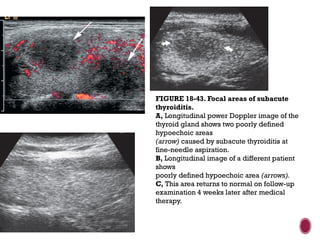

FIGURE 18-43. Focal areas of subacute

thyroiditis.

A, Longitudinal power Doppler image of the

thyroid gland shows two poorly defined

hypoechoic areas

(arrow) caused by subacute thyroiditis at

fine-needle aspiration.

B, Longitudinal image of a different patient

shows

poorly defined hypoechoic area (arrows).

C, This area returns to normal on follow-up

examination 4 weeks later after medical

therapy.

FIGURE 18-43. Focalareas of subacute thyroiditis. A, Longitudinal power Doppler image of the thyroid gland shows two poorly defined hypoechoic areas (arrow) caused by subacute thyroiditis at fine-needle aspiration. B, Longitudinal image of a different patient shows poorly defined hypoechoic area (arrows). C, This area returns to normal on follow-up examination 4 weeks later after medical therapy.